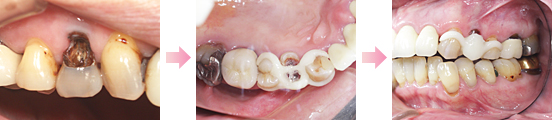

症例1 ・・・約10年間ほとんど変化ありません。